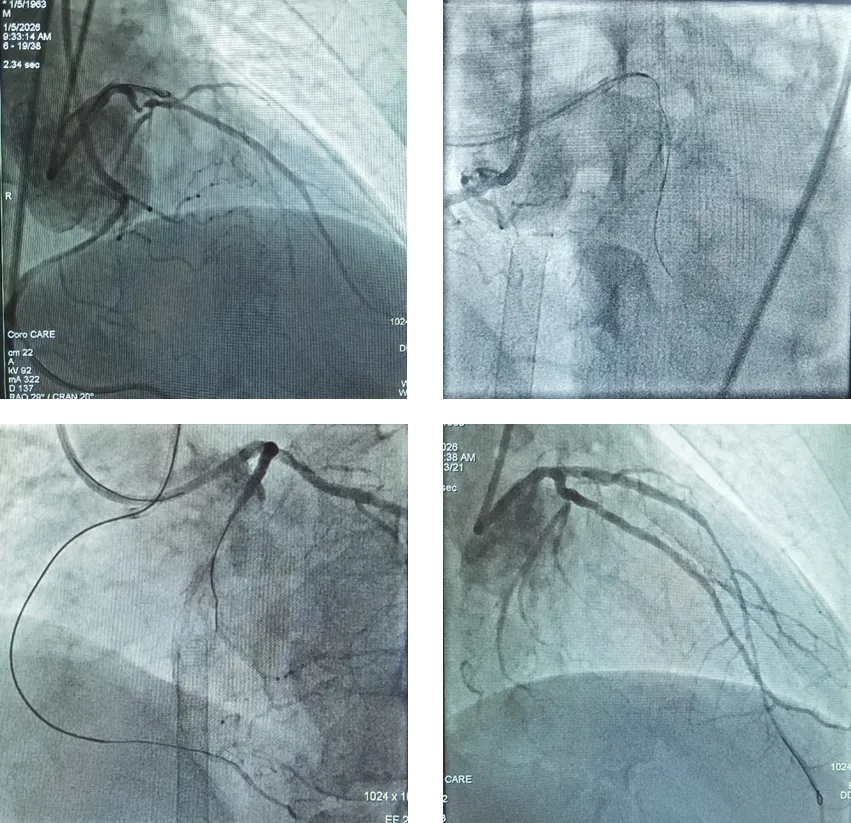

在心内一科,他被确诊为急性非ST段抬高型心肌梗死、慢性心力衰竭急性加重。患者心脏明显扩大,进一步的检查揭示了病情的极端复杂性——冠脉造影结果显示为 “三支病变、双支闭塞”,即心脏最主要的三条供血血管均存在严重狭窄,其中两支已完全堵死。更令人揪心的是,其心脏射血分数仅剩10%(正常值≥50%),这意味着他的心脏泵血功能已严重受损,生命岌岌可危,需要考虑心脏移植。

手术当天,我院急诊ECMO团队率先精准建立血管通路。随着这套“人工心肺”系统启动,患者衰竭的心脏及部分肺功能得到替代,全身血液循环与氧供得以稳定维持。在ECMO的全程护航下,心内一科介入团队精准实施冠脉血运重建手术,成功开通两支完全闭塞的血管及另一支严重狭窄的血管,并精准植入支架,彻底恢复了心肌的血液供应。整个手术过程如履薄冰,每一个操作都关乎生死,凭借团队的精湛技艺与密切配合,患者平稳度过术中最危险阶段。